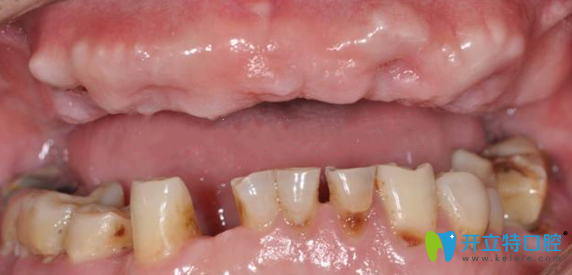

手術(shù)前:

在南京金臺(tái)口腔田忠奎院長(zhǎng)診斷,張叔的牙齒屬于半口牙缺失,牙齒根部有的已經(jīng)壞掉。目前有兩種解決辦法種植牙和烤瓷牙,田院長(zhǎng)科普了種植牙和烤瓷牙的區(qū)別后,張叔毫不猶豫的選擇了即刻種植牙齒,安全有效,節(jié)省時(shí)間,立拔立種,當(dāng)天種當(dāng)天用。